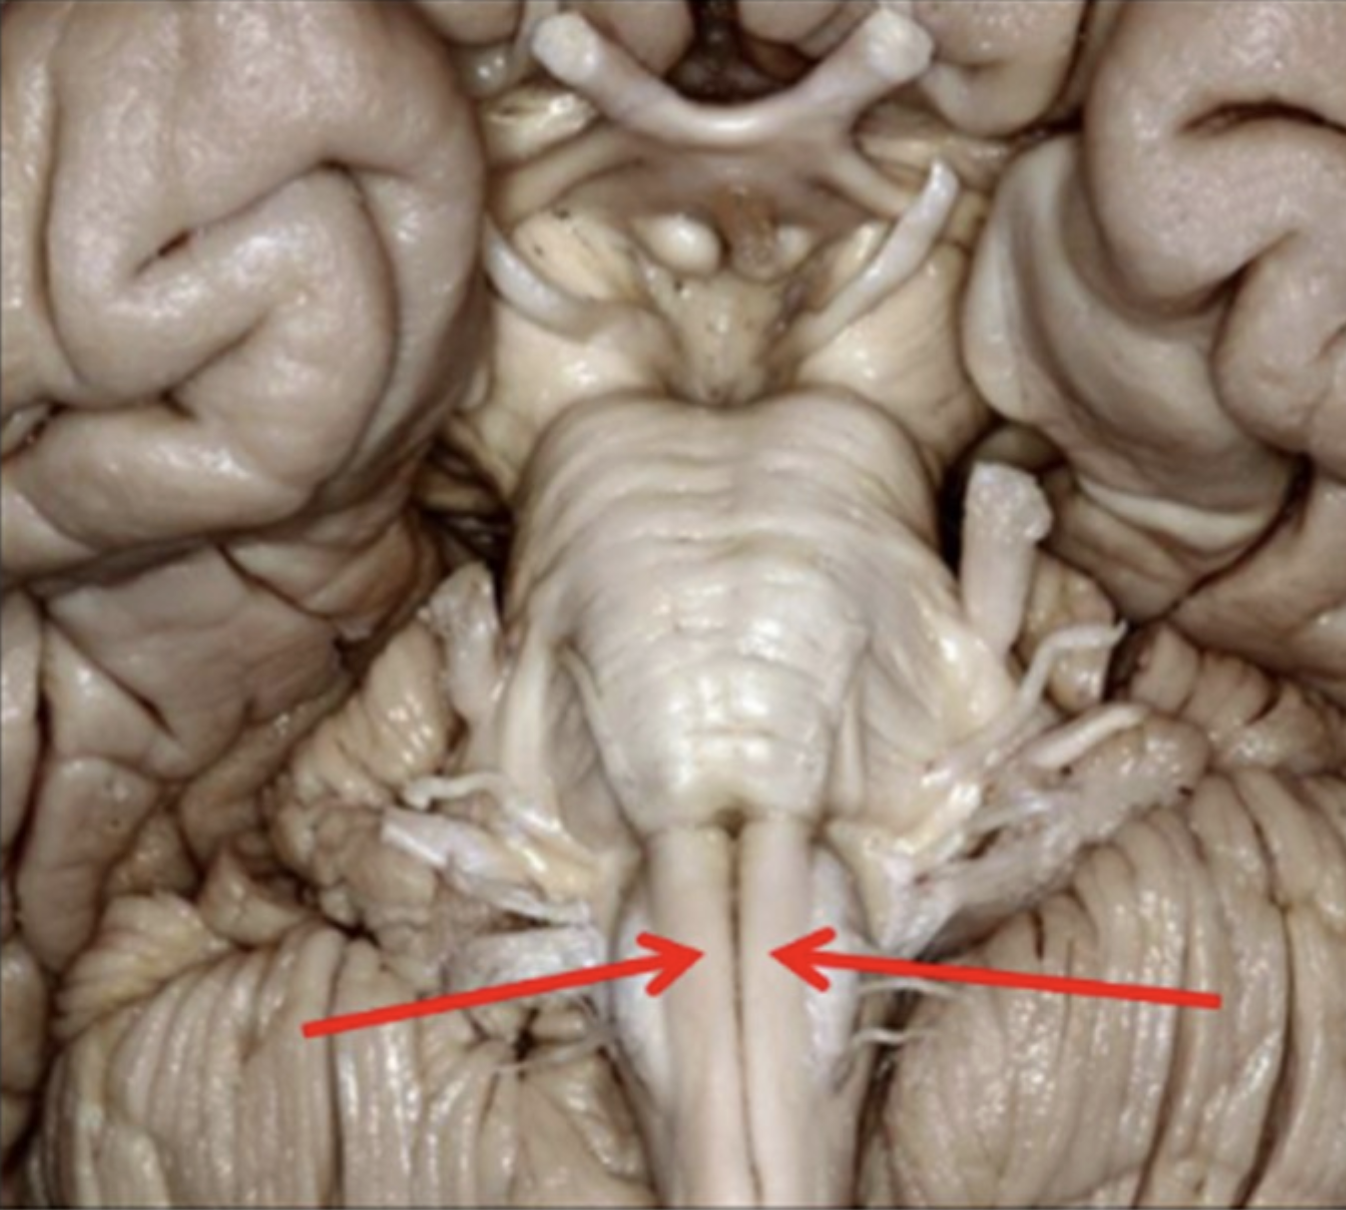

Red arrows

Pyramids

Where does the main descending pathway decussate?

Pyramids medulla